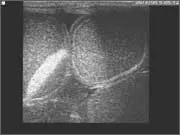

Thoracic and abdominal ultrasonography

This is a key diagnostic technique in the hospital and the technology has advanced to such a degree that we are able to image blood flowing within the heart and collagen fibre misalignment in tendons.